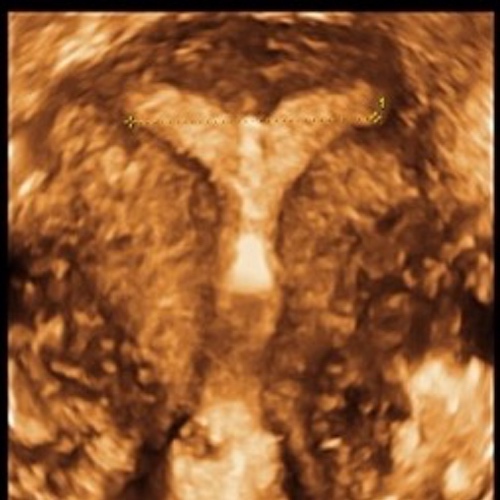

Hierzu vermessen wir die Gebärmutter mittels 3D-Vaginalsonographie und erzeugen eine dreidimensionale Darstellung der Gebärmutter und können so auf alles aufmerksam werden, was wichtig zu wissen ist. So können wir dann gemeinsam das System finden welches sich perfekt in Ihre Gebrämutterhöhle einpasst.

Hier einige Beispiele für das 3D-Counseling:

3D Bild eines perfekt sitzenden IUBTM-Kupferperlenballs.

Man sieht die relativ dünne Muskulatur am oberen Ende der Höhle (hier würde eine Kupferkette z.B. nicht verankert werden können). Auch fällt auf, dass die Höhle nur die 15mm Durchmesser "zur Verfügung" stellt. (Die kleinste herkömmliche Spirale braucht fast doppelt so viel Platz).